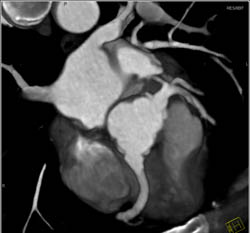

3D and MPR Sequence of Right Coronary Artery (RCA)